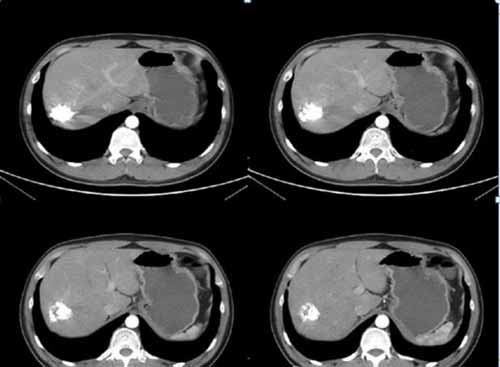

(手術(shù)過程:通過DSA下動脈造影,找到供血動脈,注入栓塞劑進(jìn)行栓塞。)

(術(shù)后復(fù)查肝血管瘤固縮,栓塞劑沉積良好,無復(fù)發(fā))